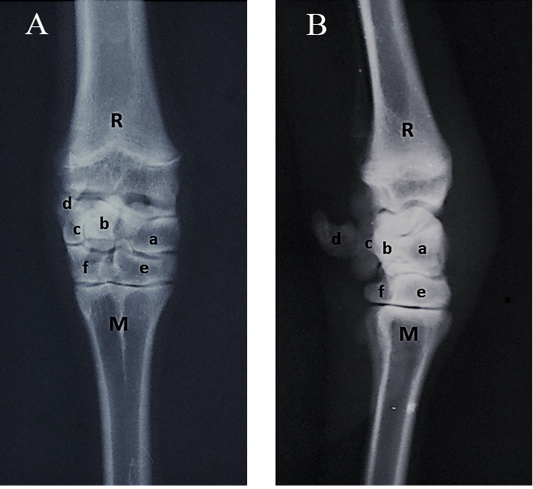

Radiographs of the carpal joint. (A) Dorsopalmar view, (B) Lateromedial view. R- Radius; M- Metacarpus; a- Radial carpal bone; b- Intermediate carpal bone; c- Ulnar carpal bone; d- Accessory carpal bone; e- Fused second, third carpal bone; f- Fourth carpal bone.